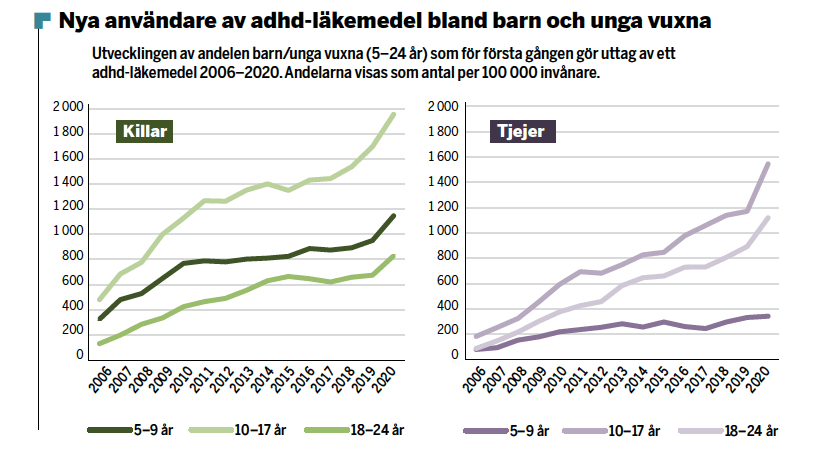

2021 förskrevs medicin mot ADHD – så kallad centralstimulantia – till cirka 146 000 människor i Sverige. Det utgör 1,5 procent av den totala befolkningen och antalet nydiagnostiserade personer ökar markant för varje år. Dessutom har på vissa håll antalet barn och ungdomar med autismdiagnos, vilket tidigare uppgått till ungefär en procent, ökat till uppemot tre procent.